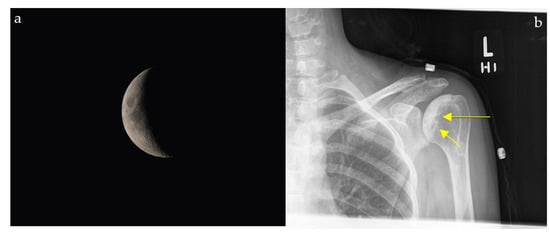

Cosmic Signs in Radiology: A Pictorial Review

Pattern recognition remains a cornerstone of radiologic interpretation, as it facilitates a confident and comprehensive differential diagnosis. Certain pathologies present with specific and highly recognizable patterns on imaging modalities. These patterns can resemble familiar real-life phenomena, including cosmic bodies that surround us. We present in this article a compilation of radiologic signs across various modalities that take inspiration from cosmic phenomena. For each sign, we summarize its defining imaging appearance, typical clinical context, and common pitfalls; where available, we note diagnostic performance (e.g., sensitivity/specificity) to guide appropriate weighting in practice. By coupling memorable imagery with succinct clinical guidance, this pictorial review aims to support a faster, more accurate pattern recognition that is applicable in both low-resource and tertiary care settings, while recognizing that these signs function as educational aids rather than validated diagnostic tests. In familiarizing themselves with these classic signs, training radiologists can benefit from an engaging and memorable way of recognizing various pathological conditions. Full article

Figure 1